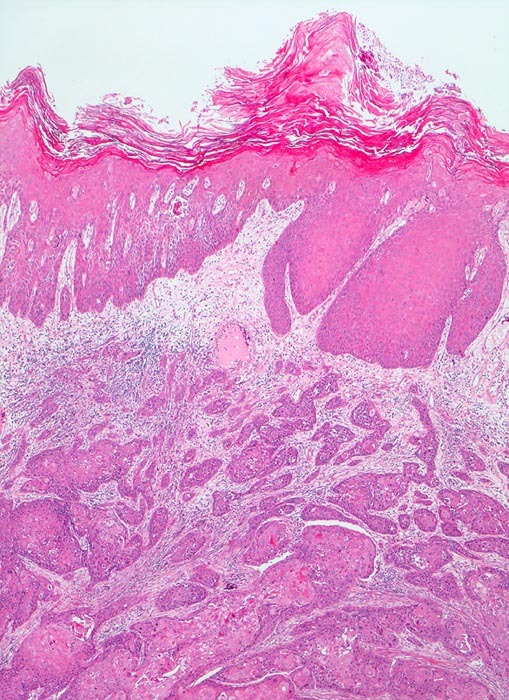

Verhornendes Plattenepithelkarzinom

Harnblase

Die Harnblasenoberfläche wird ausgekleidet durch ein stark verhornendes Plattenepithel mit Atypien. Das darunterliegende Stroma wird infiltriert von plattenepithelial differenzierten Tumorzellsträngen.

Plattenepithelkarzinome treten als Folge chronischer Entzündungen auf. (Dauerkatheterträger, Zyklophosphamid Langzeittherapie mit Zystitis, Bilharziose).